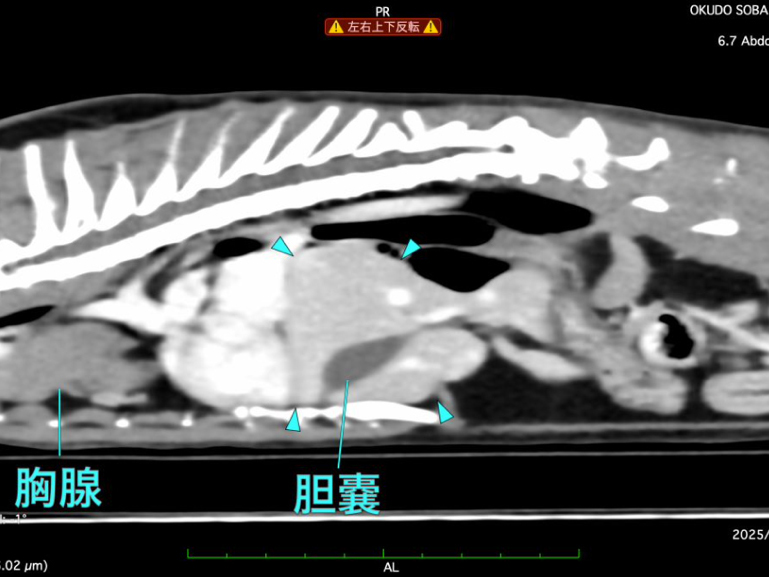

詳しく調べるためにCT検査を行った結果、「腹膜心膜横隔膜ヘルニア」と診断されました。

CT検査にて手術前評価